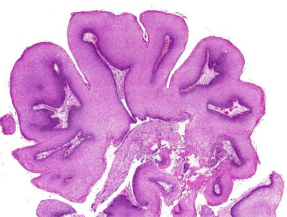

Hiperplasia patológica:  endometrial. Aumento de estrógenos, con desequilibro del cociente estrógenos/progesterona → hiperplasia de glándulas endometriales.